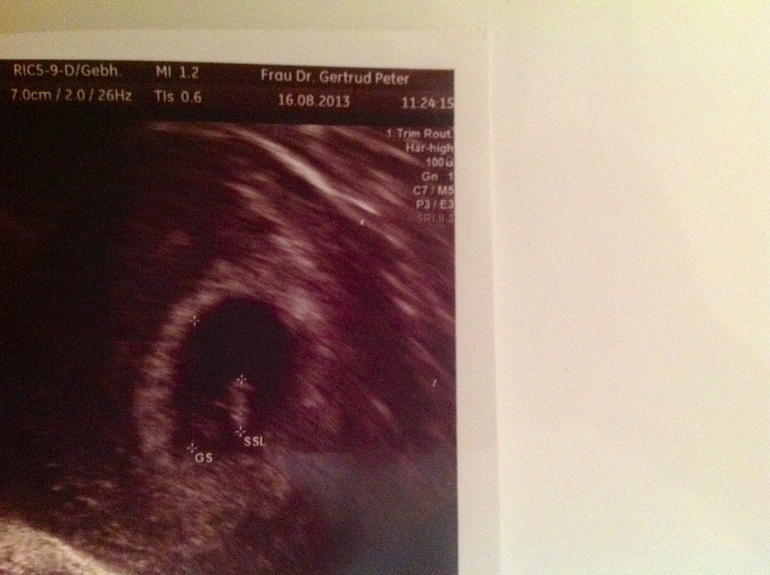

Пока все у нас хорошо, сердцебиение прослушивается, размер ПЯ 1,52 см, а сам эмбриончик 0,5 см. Анализы все в норме...... Но без НО , конечно, не бывает.... У меня нет одной половины щитовидной железы( операция в феврале!) до беременности ттг был 1,9 , таблетки не принимала, половинка справлялась сама, а тут он подпрыгнул до 3,4 , это очень высокий показатель, да еще для такого маленького срока. Прописали мне Тироксин 50 . Сказали будем наблюдать. Записалась к эндокринологу еще , поговорю еще с ним. Как же я переживаю, только бы с бусинкой все было в порядке.